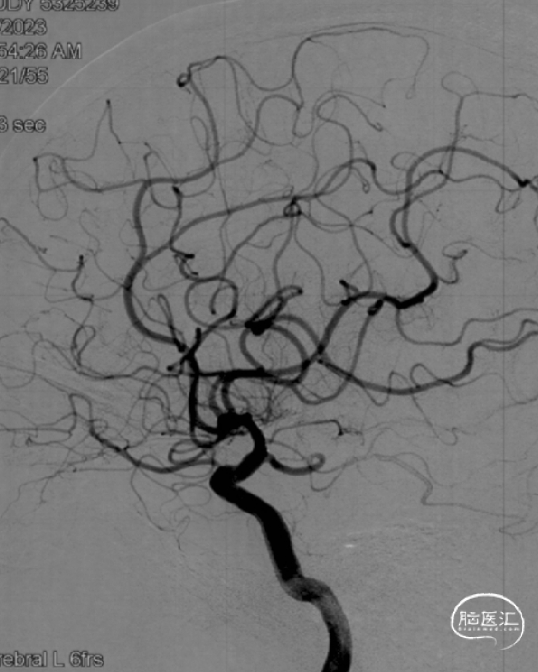

➤术前DSA检查

右侧大脑中动脉重度狭窄,左侧前循环未见明显异常。

病变部位: 右侧大脑中动脉M1段重度狭窄;狭窄率: 75.6%;狭窄长度: 6.10mm;参考远端血管直径: 1.27mm。

2023-02-06 6M-FU (正位)

2023-02-06 6M-FU (侧位)